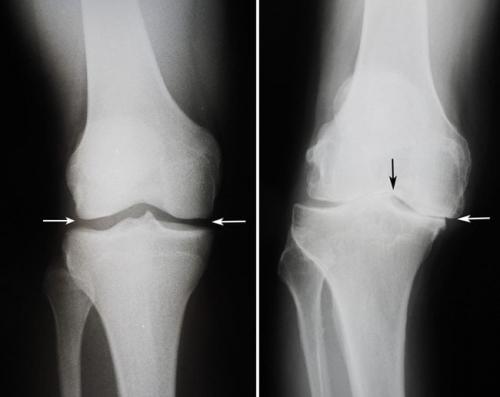

Колени в обратную сторону болезнь. Какие бывают болезни коленного сустава: список самых распространенных

частые патологии опорно-двигательного аппарата. Около 15% пациентов ортопедо-травматологических стационаров попадают туда именно из-за проблем с коленями. Давайте посмотрим, какие бывают болезни коленного сустава.

При отсутствии лечения некоторые травмы и заболевания колена могут приводить к снижению трудоспособности и даже инвалидности. Если вас беспокоят боли,или другие неприятные симптомы – немедленно идите к врачу! Своевременная медицинская помощь поможет вам избежать тяжелых последствий.

В зависимости от причин возникновения все болезни коленных суставов можно разделить на несколько больших групп. Для каждой из них характерны свой механизм развития и симптоматика.

Виды заболеваний коленных суставов:

- воспалительные. Характеризуются развитием инфекционного или асептического воспаления различных структур коленного сустава. Могут возникать в любом возрасте. Причины патологиизанесение инфекции в сустав или наличие воспалительного процесса в организме.может быть как острым, так и хроническим. Воспалительные процессы также могут развиваться на фоне длительного течения;

- дегенеративно-дистрофические. Чаще встречаются у пожилых людей и лиц, которые постоянно выполняют тяжелую физическую работу. Дегенеративные процессыэто следствие старения организма, которое сопровождается замедлением метаболизма и кровообращения в суставах. Под действием провоцирующих факторов (физические нагрузки, нехватка кальция, обменные нарушения) суставные хрящи начинают разрушаться, что приводит к развитию патологии. Дегенеративно-дистрофические заболевания имеют хроническое, медленно прогрессирующее течение;

- травматические . Возникают сразу после травмы или позже, в более отдаленном периоде. Причиной может быть падение,, удар по колену или сдавление ноги тяжелым предметом. Травматические заболевания могут приводить к нарушению функционирования коленных суставов, трудностям при ходьбе и даже инвалидности. Их своевременное лечение помогает избежать нежелательных последствий;

- опухолевые . Новообразования в области колена могут быть доброкачественными и злокачественными. К первым относят остеому и, которые хорошо поддаются лечению. Ко вторым относятся множественная миелома, хондросаркома, остеогенная саркома. Как и любые злокачественных опухоли лечить их сложно. Развиваются они редко.